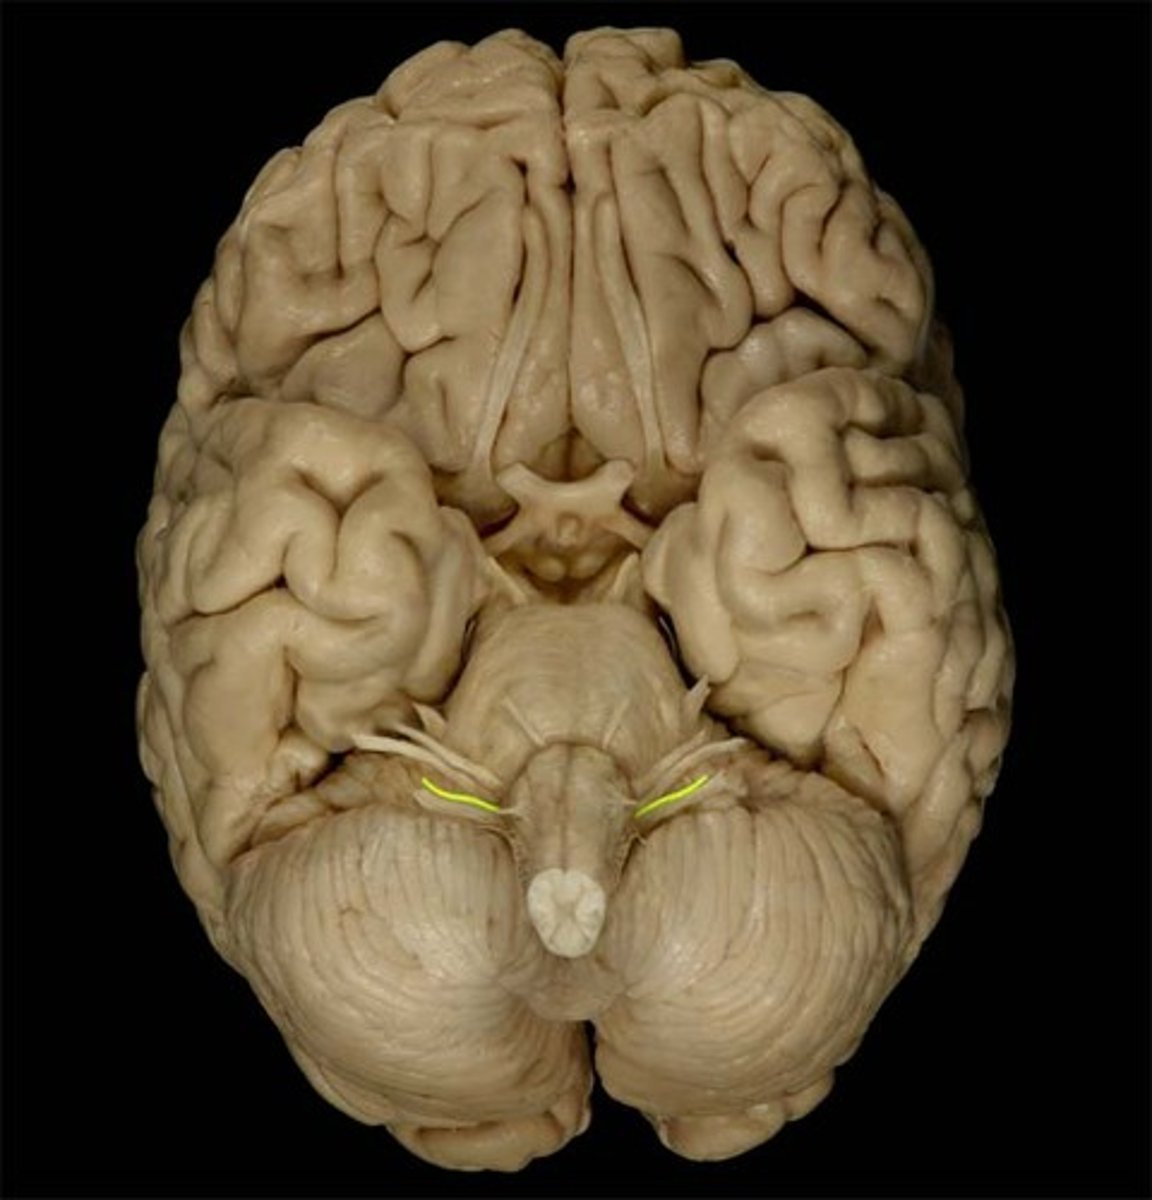

Superior Dorsal View of brain

Gyri

Sulci

Longitudinal Cerebral Fissure

Frontal Lobe

Parietal Lobe

Occipital Lobe

Central Sulcus

Lateral Sulcus

Somatomotor Area

Somatosensory Area

Cerebellum

Olfactory Bulb

Optic Chiasm

Mammillary Bodies

Pons

Medulla Oblongata